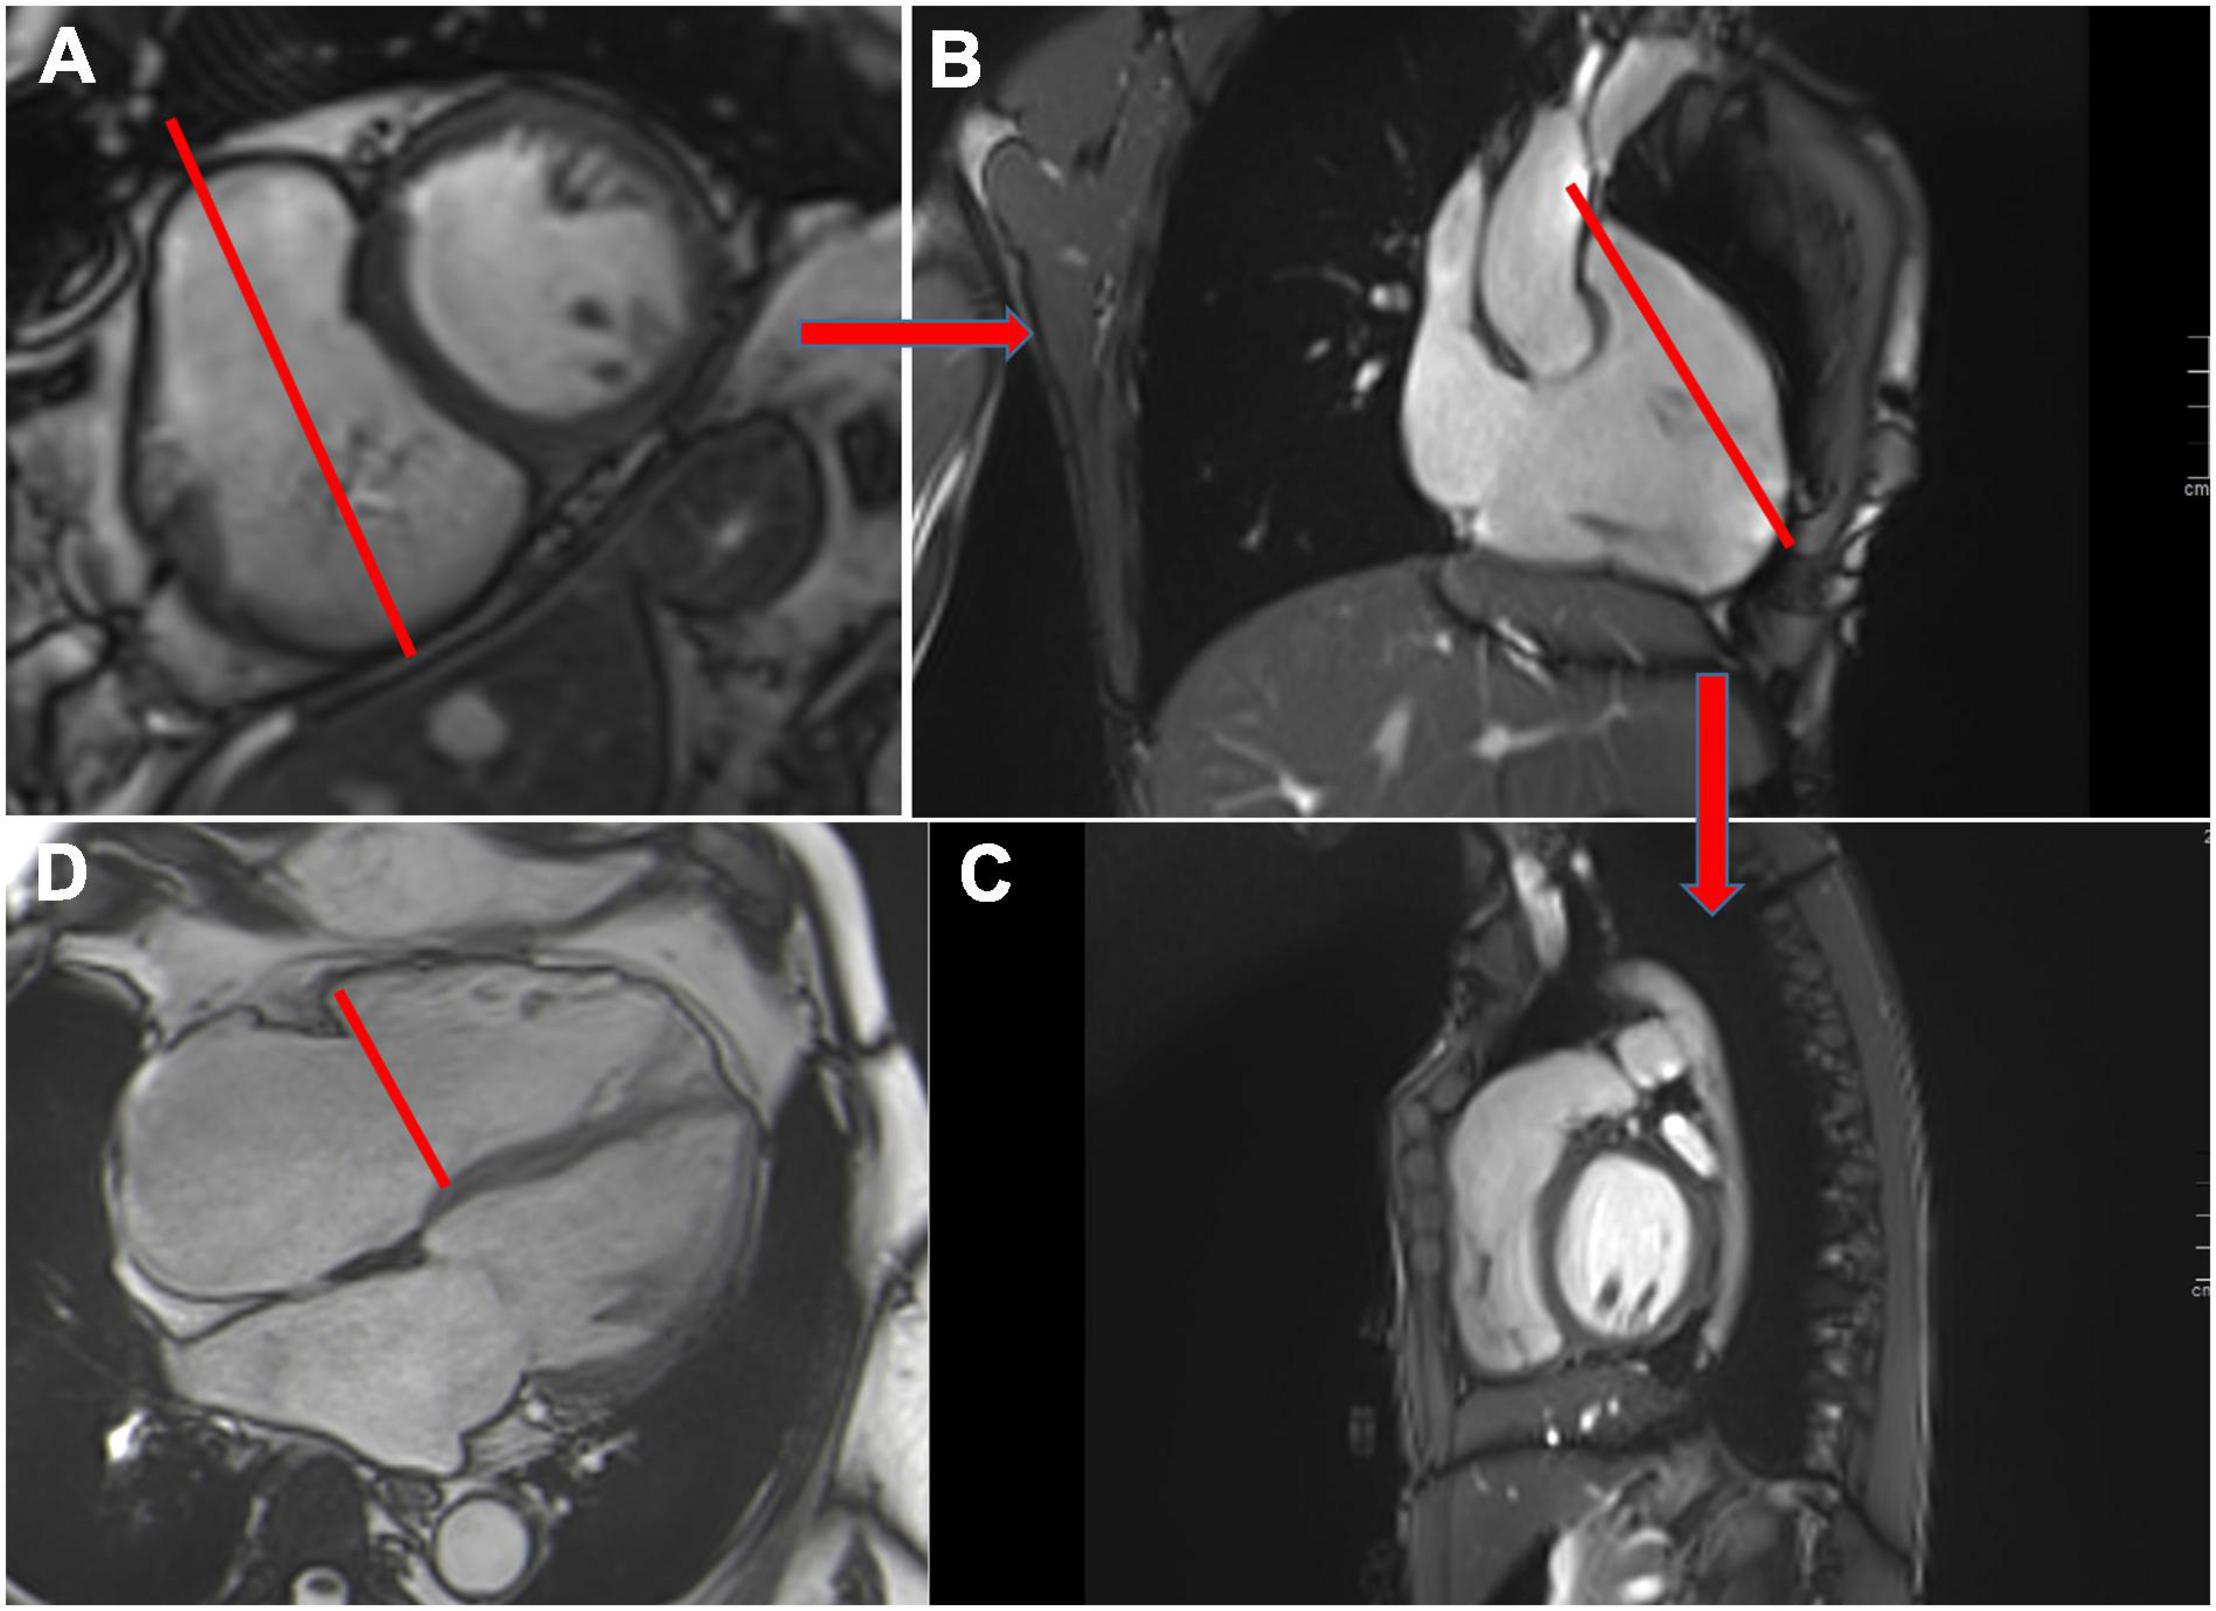

- A stack of contiguous cines through-plane on the MV and perpendicular to the mitral commissure to cover all of the mitral scallop; from A1–P1 to A2–P2 and A3–P3 (Figure 1).

Figure 1. Anterior and posterior mitral valves and their scallops (A1, A2 and A3 and P1, P2, P3) visualized in diastole using balanced steady-state free precession (bSSFP) cine images in the plane of the mitral valve (A). Cine 4 chamber view in a patient with posterior and anterior mitral valve prolapse (red arrows) (B). Example of mitral annular measurement from the anterior commissure to the posterior commissure (red line) in the 2-chamber view (C). A central mitral regurgitation (flow void in the left atrium, red arrow) secondary to mitral annular dilatation visualized in the 4-chamber view (D).

Leaflet motion abnormalities can be described as classically defined by echocardiography (prolapse, flail) (Figure 1). However, a flail leaflet in CMR can be masked by the regurgitant flow. Maximum mitral leaflet thickness is measured in diastole. Standard long-axis cine images are also informative for visualizing and sizing the mitral annulus (14). With CMR reference ranges, mitral annular dilatation, one of the mechanisms in secondary MR, can be identified. The mitral annular diameter is measured from the anterior commissure to the posterior commissure in the diastole (Figure 1). In primary MR (mitral valve prolapse especially), CMR can detect mitral annulus disjunction, a frequent component of myxomatous mitral valve disease (15) using standard long-axis cine images.